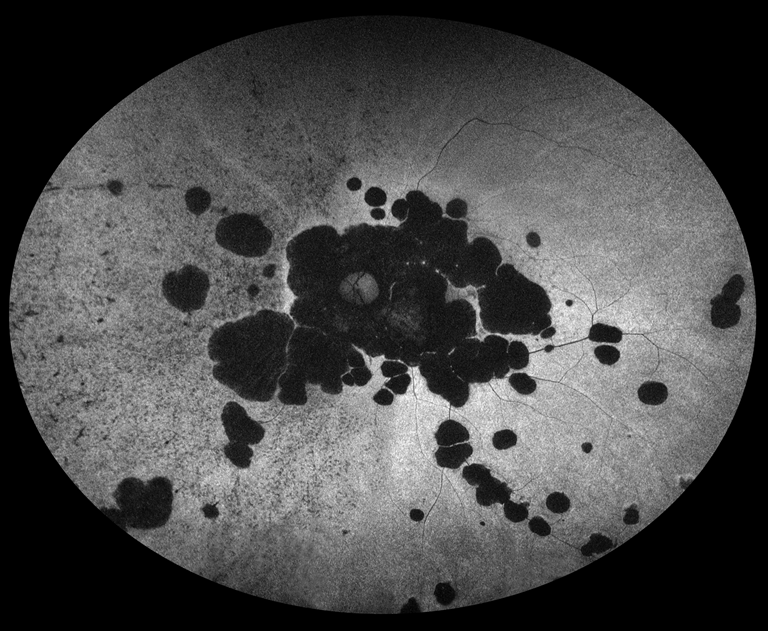

Atypical Retinitis Pigmentosa with Rod-Cone Dysfunction

Presented by Judith Gulian, BSc, OCT-CThis photograph received 3rd Place in the category "Fundus Autofluorescence" and was displayed at the 2024 ASCRS/OPS Society Exhibit.